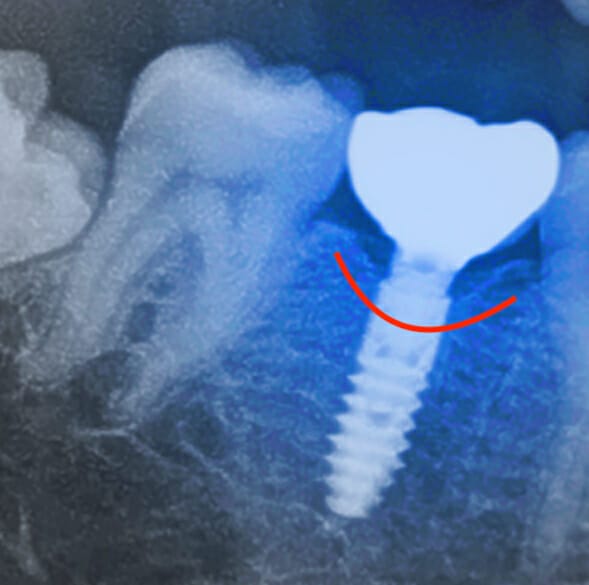

Well, an implant is one cylinder-shaped screw that supports a crown (you know, the tooth part that you can see above the gums).

A molar tooth has 3 and sometimes 4 roots to support it's crown. When you replace a molar, the implant-crown isn't resting on 3-4 implants, it's supported by only one.

This gives you a fairly large bulky tooth (or crown) portion supported by a very thin implant portion. While the image below is an exaggeration of the size difference between crown and implant, the overall implant-crown form is kind of like a lollipop.

Even when you're replacing a tooth with only 1 root, the implant will have less flare and contour in comparison.

Why does all of this matter?

First things first, let's talk about the flare. A natural tooth has a root that flares out gradually as it moves up to the gum line where the crown of the tooth begins. An implant has less flare. The result is that the implant-crown is much wider than the implant itself. So you get large pockets under the implant-crown. These pockets trap and retain more food and are harder to clean. This puts your implant and surrounding gums at greater risk for inflammation and bone loss.